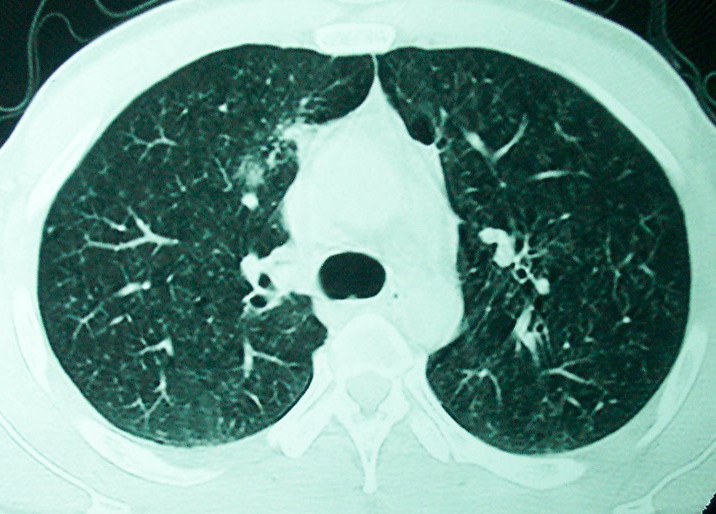

m      37y      发热   咳脓痰月余      ct肺脓肿但住院抗炎治疗后双肺内结节不知该如何解释

治疗后见左肺下野病灶较前缩小但双肺内结节影似无变化请较各位老师该如何下结论    治疗前wbc14.5 治疗后wbc 11.0

血源性肺脓肿,一般由原发感染灶引起脓毒败血症,在肺部形成小脓肿,病变变化快,容易形成肺气囊,脓气胸,主要与转移瘤鉴别,通过临床病史可分

结合临床发热,咳痰考虑为血源性肺脓肿,不过双肺结节又在肺的边缘,还是小心一点,抗炎后复查吧

除了肺内多发结节和左肺下叶的浓疡病灶,还应注意满肺散在的小结节影,还有右上肺前段支气管内膜不光整这些细节,结合病史,肺内多发结节应考虑结核性肉芽!

如果你仔细的同层面对比,你会发现所有的病灶均有比较明显的吸收、缩小。病变的形态,特别是脓肿的形态、壁的厚薄、内壁均有很大的变化,均在往好的方面发展。与临床症状、血像均符合,治疗效果比较显著,就是肺脓肿并双肺的化脓性炎症灶。